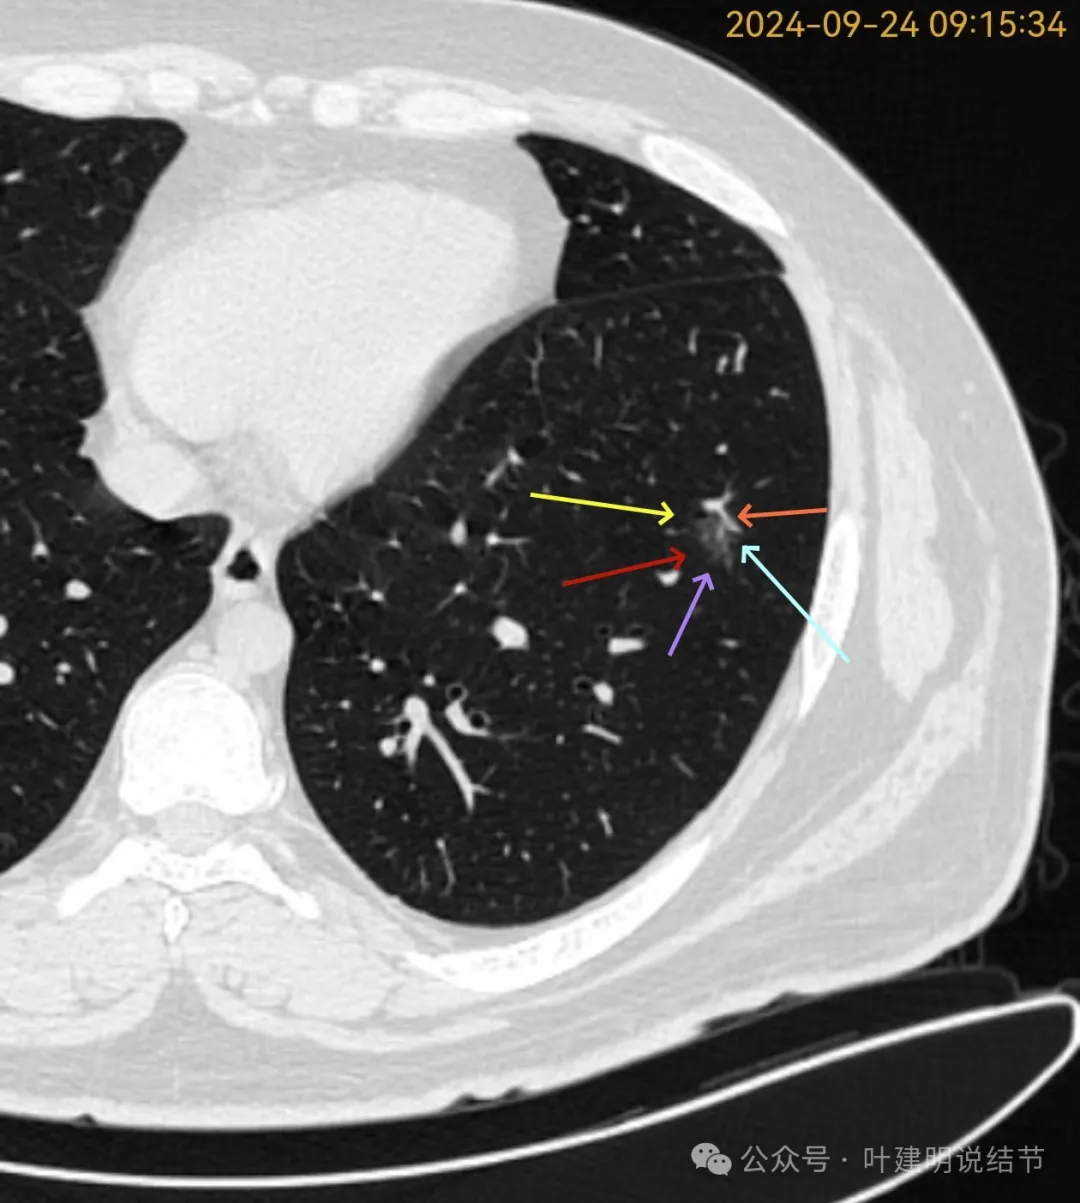

再看2024年9月复查的片子:

病灶出现,磨玻璃密度。有微小血管与细支气管通气征。

邻近细支气管扩张、边缘细毛刺、整体轮廓清。

有毛刺征,整体轮廓清,与血管之间间隙消失。

毛刺、血管征、邻近支气管扩张、整体轮廓清,病灶与血管间隙消失。

有少许偏实性成分,整体轮廓清。

纯磨密度,不太纯,血管贴边,血管与病灶间隙消失,整体轮廓与瘤肺边界清。

血管弯征可见、细毛刺明显、细支气管扩张,血管进入。

密度总体不高,轮廓与边界清楚。

密度较淡,轮廓较清。

边缘区密度淡且较纯,轮廓清楚。